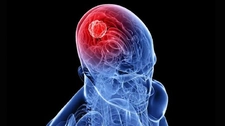

Annemin kafasında tmör var dedi doktoru kötü huylu mu iyi huylumu bioksi sonucunu bekliyoruz kafa da iyi huylu da çıkabiliyor mu parça almadan önce kafa ağrısı vardı annemde alınalı on gün oldu kafa Ağrı sı yok ne yapacağımızı bilemiyoruz bize yardımcı olabilirmisiniz

Hüsnü bey merhabalar iyi günler dilerim. Kafa dediğiniz kısmı sanırım beyin olarak düşünüyorum. Bu bölgede çıkan tümörler, benign olarak adlandırılan iyi tümörler de olabilir; malign adı verilen kötü huylu tümörler de olabilir. Bunu anlamanın en iyi yolu biyopsi sonucunu beklemektir. Çıkan sonuca göre, doktorunuz uygun bir tedavi planı oluşturacaktır. Sağlıcakla...

Merhaba Hüsnü Bey, meydana gelen kistler kötü huylu da olabilir iyi huylu da. Bu tamamen gelecek olan biyopsi sonucunda karşımıza çıkacaktır. Bu nedenle sabırla beklemekte fayda vardır. Ameliyatlı olan noktanın enfeksiyon kapmaması için şuan buna odaklanıp iyi bir bakım yapmanız tavsiye edilmektedir.